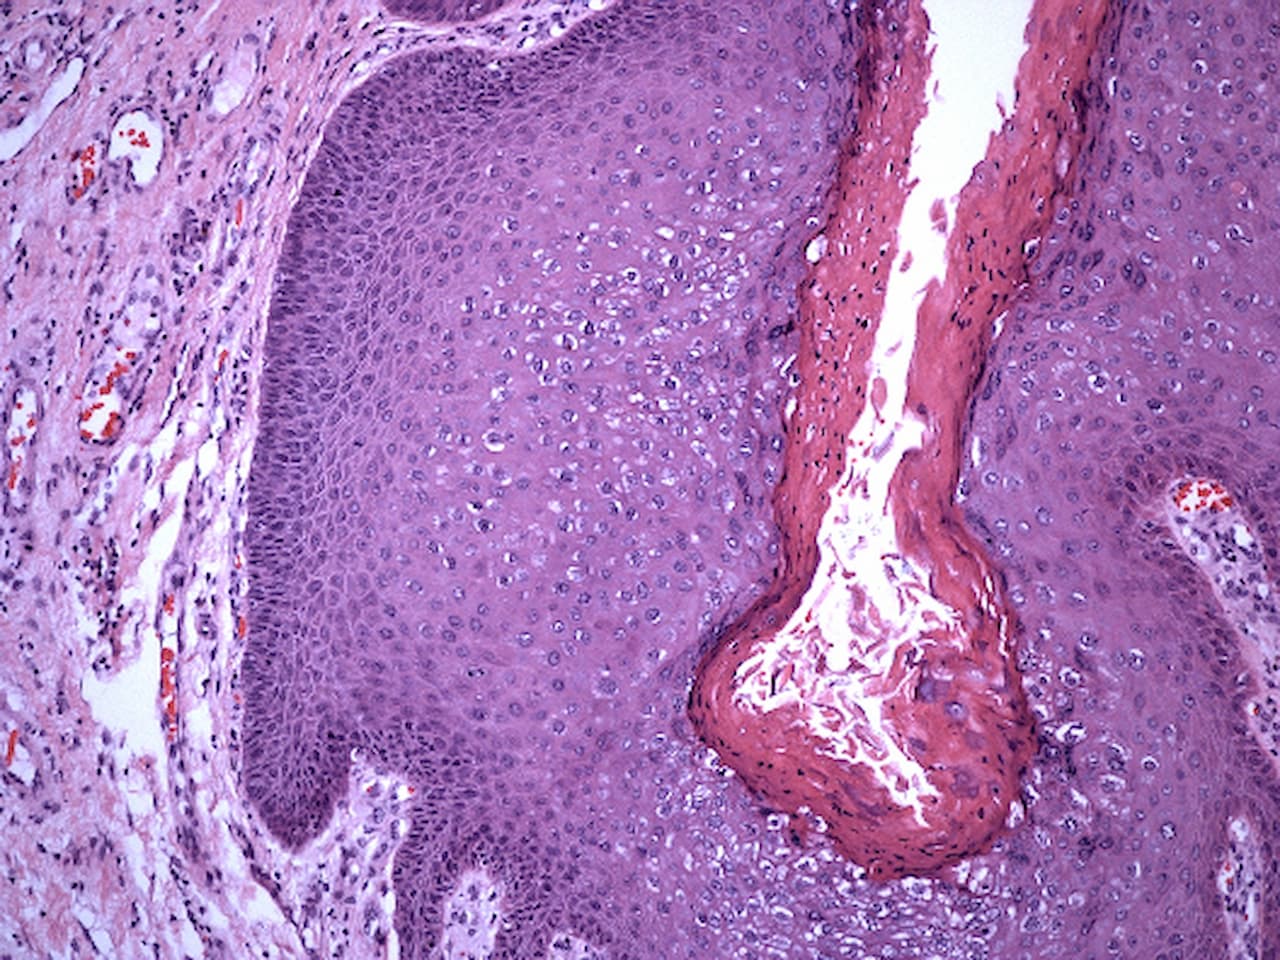

사마귀란?

사마귀는 작은 콜리 플라워와 비슷한 거친 질감을 가지고 있는 작고 단단한 물집입니다. 참고로 인유두종 바이러스(HPV)는 피부의 어느 부위에서나 자랄 수 있는 사마귀를 유발하며, 일부 HPV 유형은 악성을 일으키기도 하지만 대부분의 사마귀는 몇 년 정도면 자연적으로 없어집니다.

일반적인 사마귀는 손가락과 발가락에서 발생하는데 거칠고 단단하게 자랍니다. 발바닥 사마귀는 주로 발바닥, 발 뒤꿈치 및 발가락에서 발생합니다. 이것은 흰색의 단단한 조직으로 둘러쌓여 있는 어두운 점으로 안쪽으로 자랍니다. 편평한 사마귀는 태양에 노출 된 피부 표면에 편평한 분홍빛 또는 황갈색 반점으로 자랍니다. 필모꼴 사마귀는 눈꺼풀, 코, 목 및 겨드랑이의 피부색 플랩 또는 길쭉한 꼬리표 같은 모양입니다. 말초 사마귀는 발가락과 손가락 주변이나 아래에서 자라며 올라오면서 손톱 성장을 방해 할 수 있습니다. 생식기 사마귀는 분홍색 또는 붉은 빛을 띠며 콜리 플라워와 비슷한 형태로 3 ~ 4 개의 사마귀 군집을 형성합니다.